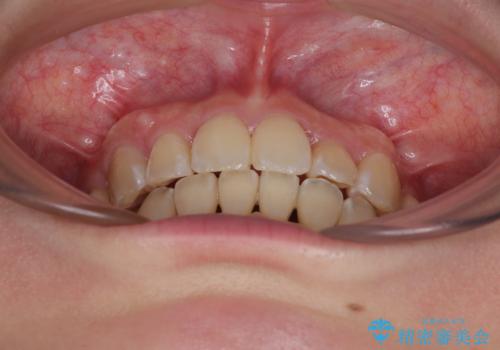

奥歯の咬み合わせ改善にはどうしても長期間を要します。

3年強とお伝えしておりましたが、予想通り3年3ヶ月で治療を終えることができました。